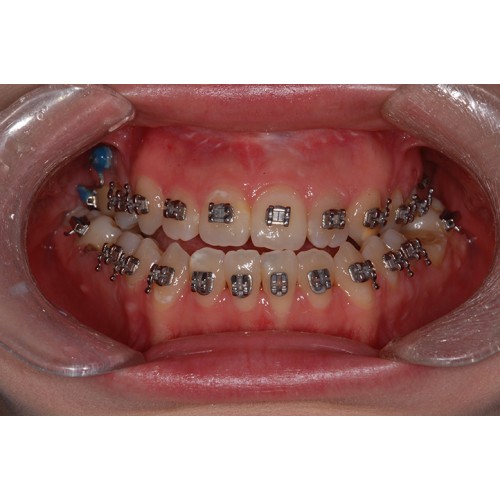

CHUNCHU'S ORTHODONTIC CLINIC# BEFORE_AFTER

춘추치과교정과를 방문해주신 분들의전후 사진을 확인해보세요.